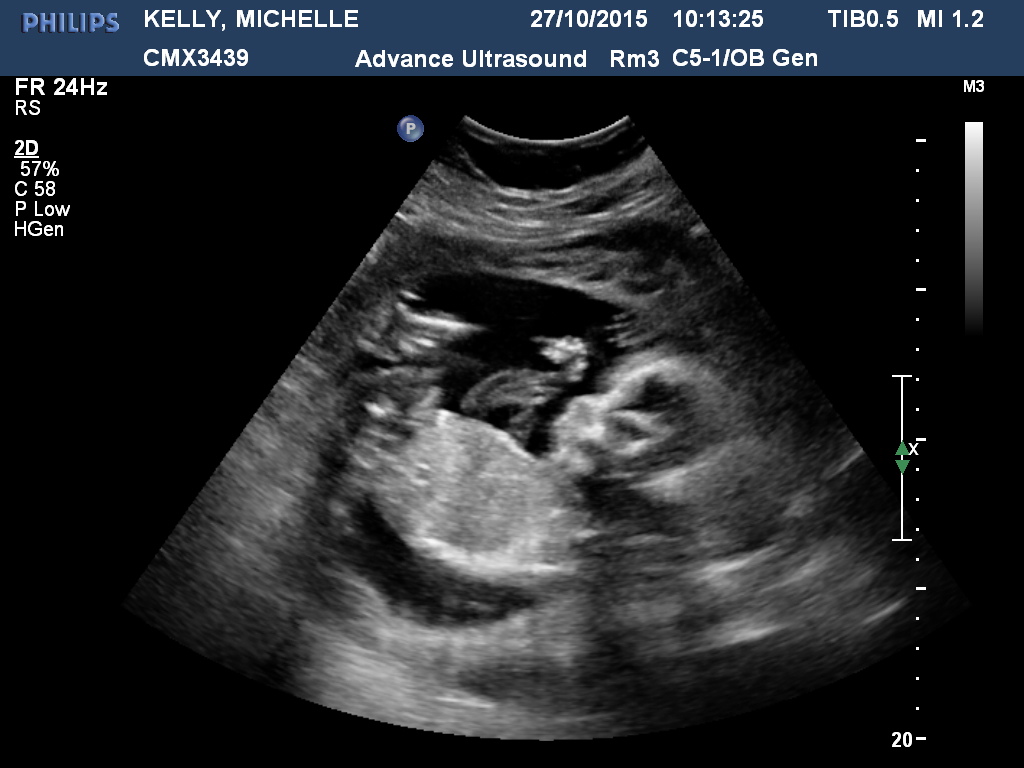

Just had our 20week scan. DH doesn't want to know the gender but I am far too impatient. Hoping I can upload a few pics and you guys might be able to see something I can't ;)

No clues. Hope you get pink.

Not seeing gender, sorry.

Maybe girl :)